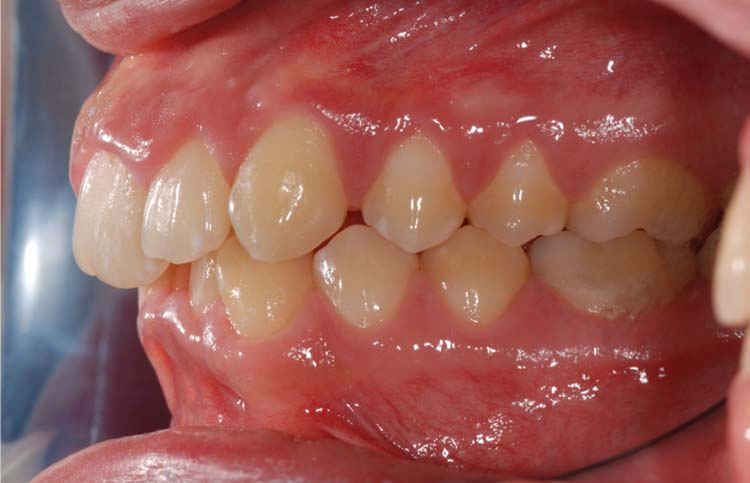

Caso clinico 1

Caso clinico 2

Caso clinico 3

Caso clinico 4

Caso clinico 5

Caso clinico 6